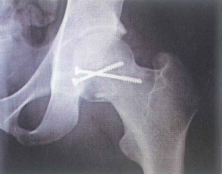

Hình 4.18. Hình ảnh sau mổ vít xốp gãy chỏm xương đùi

1.1.5. Điều trị sau mổ gãy chỏm xương đùi

Sau khi mổ kết hợp xương vùng chỏm xương đùi vững, việc vận động chủ động và thụ động biên độ khớp háng được bắt đẩu sớm nhất có thể để tránh biến chứng cứng khớp.

Khi ổ gãy chưa có dấu hiệu liền, việc tỳ đè được khuyến cáo muộn, ít nhất sau 8-12 tuần sau phẫu thuật.